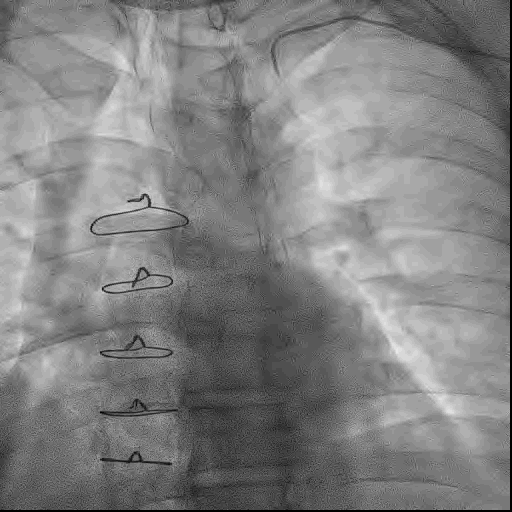

首先置入Cosair135微导管,使用XTR导丝反复尝试无法通过闭塞段,更换UB3导丝后成功通过闭塞段。

冠脉造影提示RCA闭塞钙化负荷较重,使用球囊锚定技术,小球囊反复扩张闭塞病变。

后更换微导管送入RCA中远段,并更换工作导丝至左室后支远端。

术中,球囊扩张RCA中远段后出现夹层,使用球囊压迫后复查造影TIMI血流3级,故结束手术。